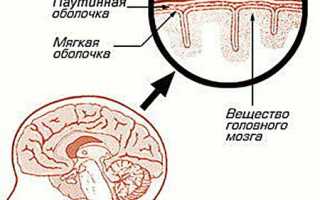

Арахноидит, затрагивающий головной или спинной мозг, представляет собой серозное воспаление уникальной структуры, находящейся между твердой верхней оболочкой и глубокой мягкой. Эта структура, напоминающая тонкую паутину, и получила название паутинная оболочка. Она образована соединительной тканью и образует настолько тесную связь с мягкой оболочкой мозга, что их часто рассматривают как единое целое.

Паутинная оболочка отделена от мягкой оболочки субарахноидальным пространством, в котором находится спинномозговая жидкость. В этом пространстве располагаются кровеносные сосуды, обеспечивающие питание данной структуры.

Из-за особенностей своего строения воспаление паутинной оболочки не бывает локализованным и охватывает всю систему. Инфекция может проникать сюда через твердую или мягкую оболочку.